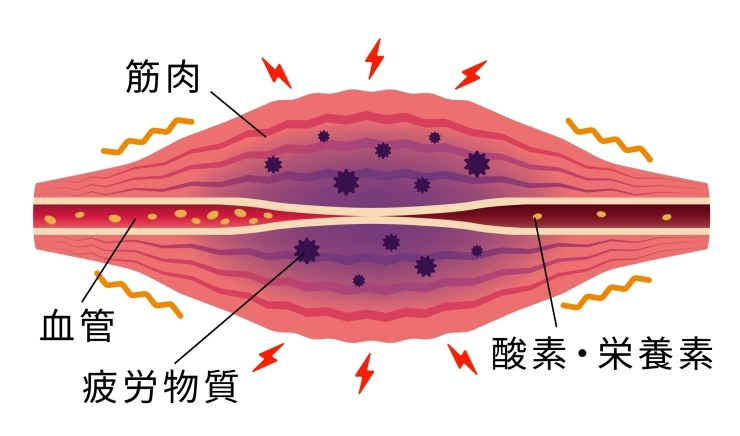

こんにちは いろは整堂 です🍀 「動き過ぎて 乳酸が溜まっている」 そんなセリフ聞いた事ありませんか? 実はこれ 今では科学的に否定されている古い常識なんです((+_+)) 乳酸は今まで 疲労物質とか 痛みの原因と考えられてきましたが今ではむしろ 体の役に立つエネルギー源の一つという事がわかってきています つまり 乳酸が溜まっているから 痛い!ダルイ! は迷信だったんですね💦 では あの疲れや筋肉痛の正体は❓...